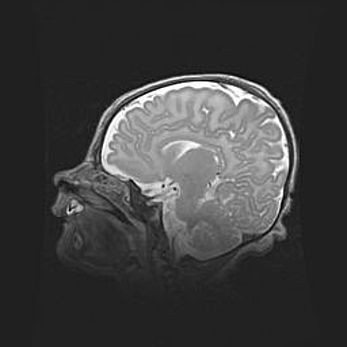

Открытая гидроцефалия.

Возраст: 9 месяцев 12 дней

Вес: 6800 г

Пол: мужской

Окружность головы: 41,5 см

Срок гестации: 28 недель

Гидроцефалия головного мозга у новорожденных имеет характерный признак: опережающий рост окружности головы приводит к визуально хорошо определяемой гидроцефальной форме сильно увеличенного в объёме черепа. Детские неврологи определяют следующие симптомы гидроцефалии у грудничков: выбухающий напряжённый родничок, частое запрокидывание головы, смещение глазных яблок к низу.